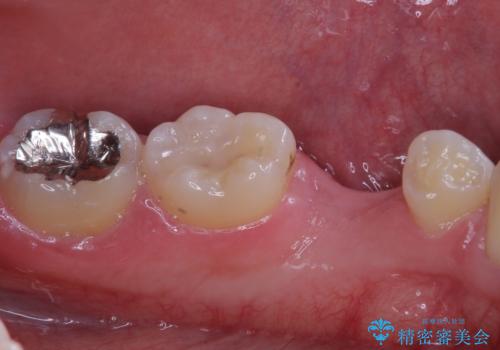

- 乳歯を抜歯したところにインプラントをしたいと来院された患者様です。

永久歯の先天欠如による乳歯の晩期残存があり、その乳歯が虫歯になってしまい保存不可能になり、他院で抜歯をし義歯を使用していた状態です。

義歯では嚙みづらいため、インプラントによる補綴をしていくこととしました。